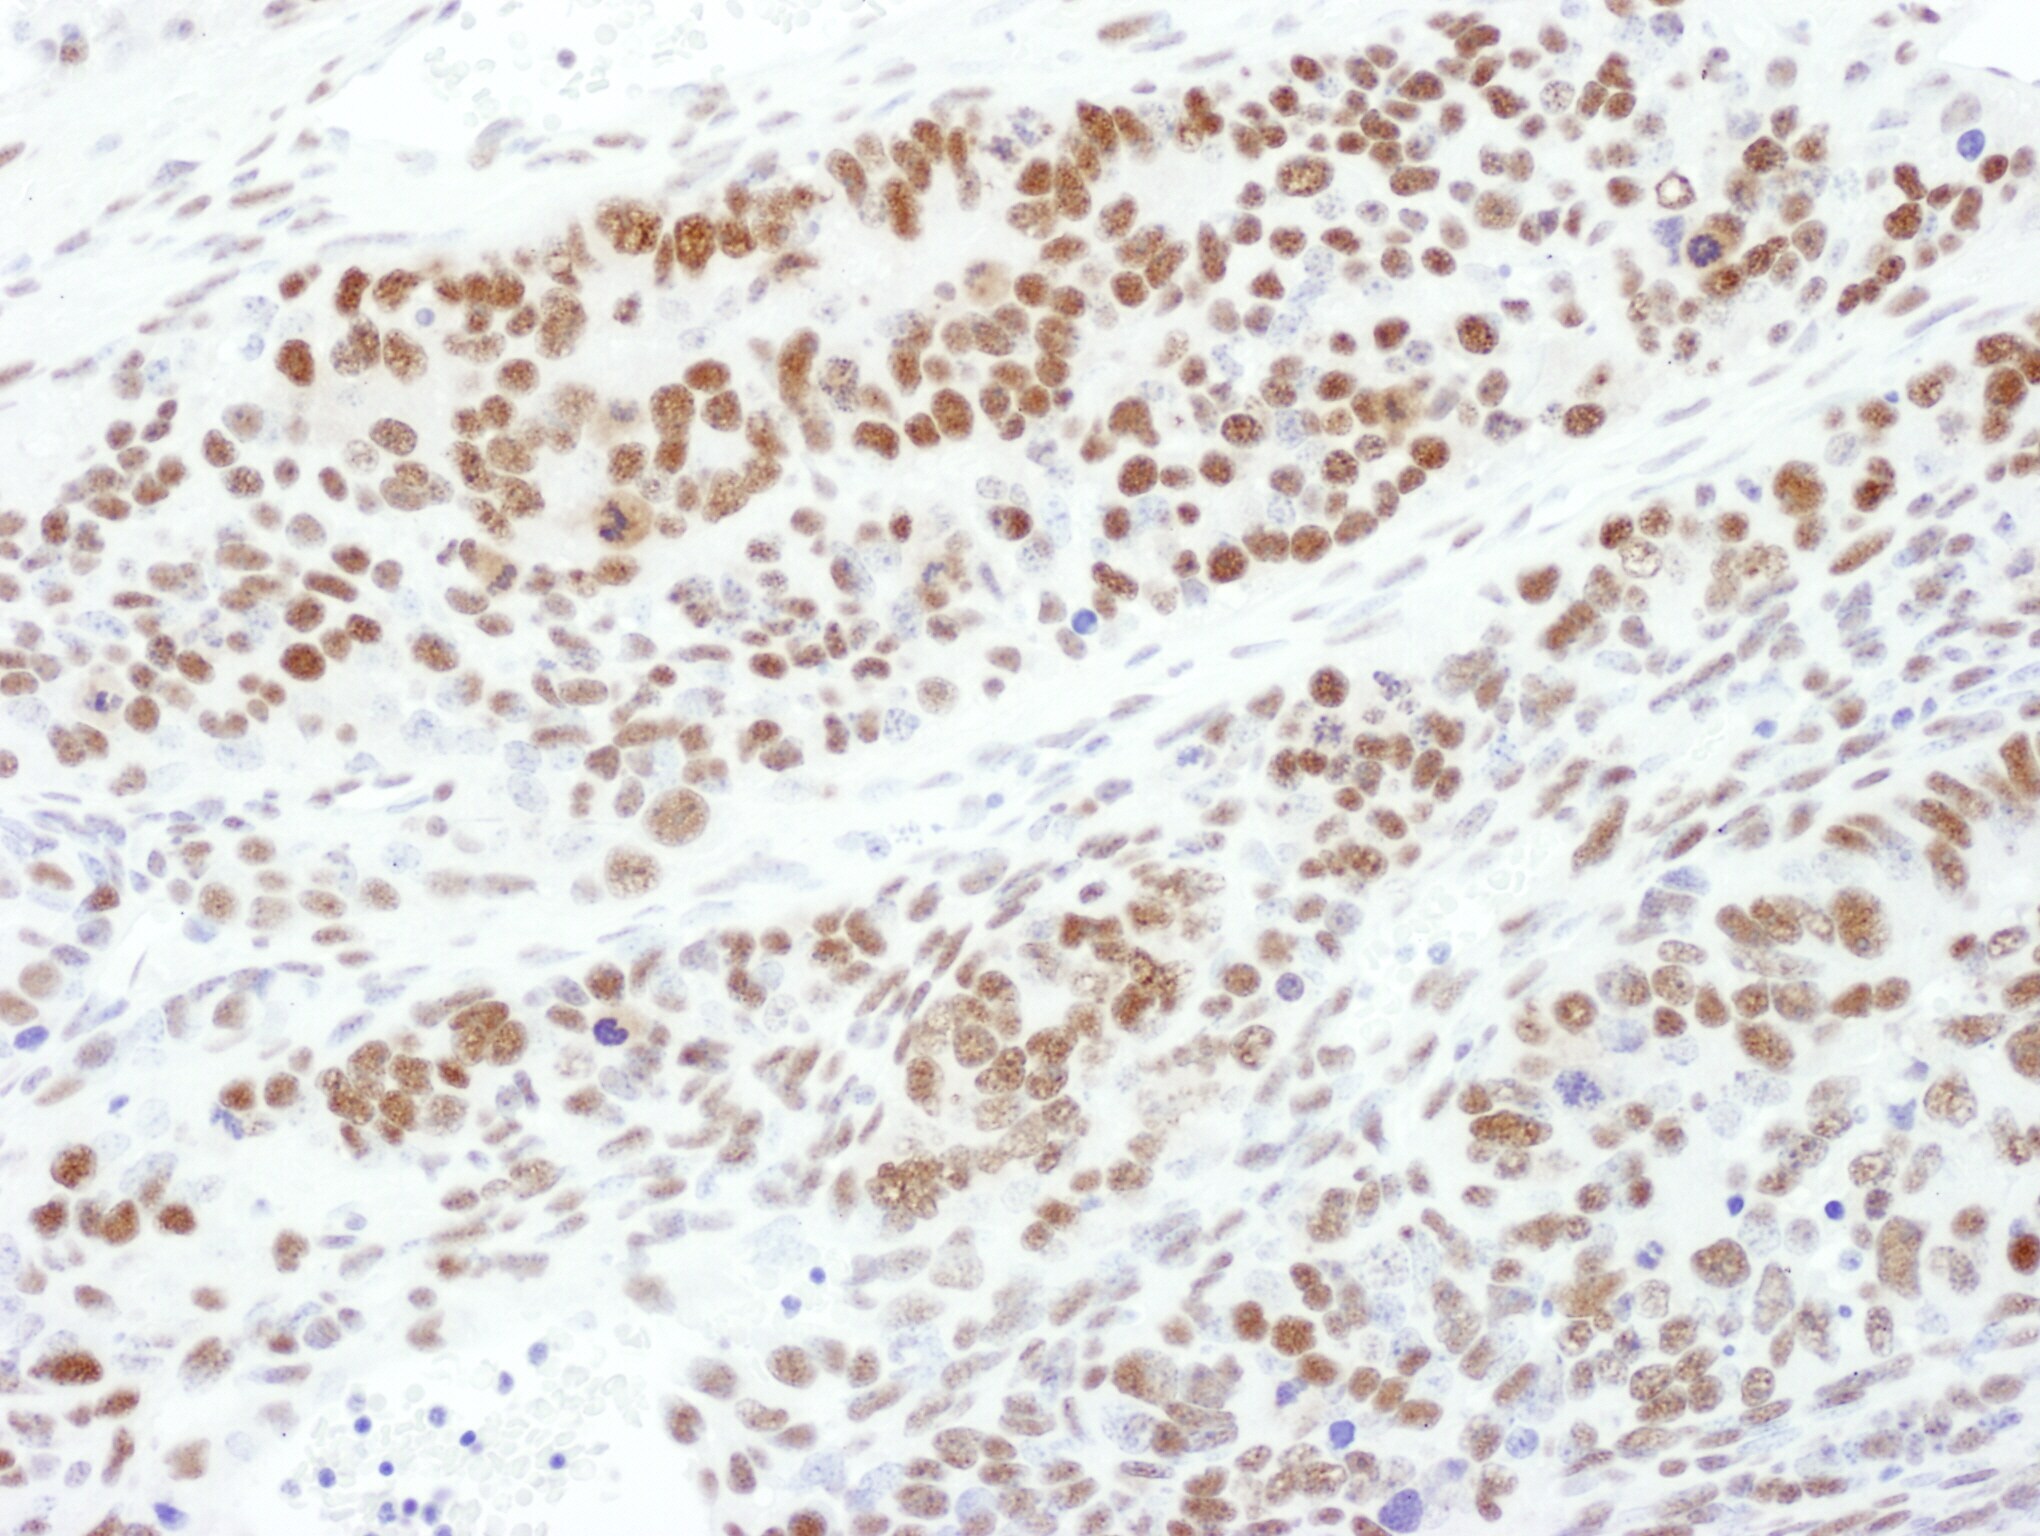

- Detection of human Phospho-MEK1 (T286) by immunohistochemistry. Sample: FFPE section of human breast carcinoma. Antibody: Affinity purified rabbit anti- phospho MEK1 (T286) (Cat. No. A303-611A Lot1) used at a dilution of 1:1,000 (1µg/ml). Detection: DAB.